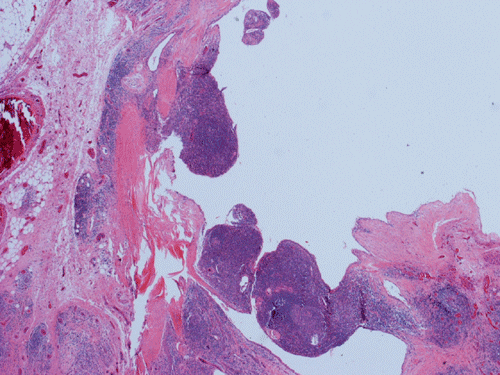

Clinical information: The patient is a 36 year-old woman who presented with a 2 cm swelling in the left side of her neck. The mass was not tender, warm, or painful. The overlying skin was unremarkable. A CT scan was performed and showed a 1.8 x 1.2 cm relatively non-enhancing lesion within the carotid sheath displacing the carotid artery anterioriorly. The clinical and imaging features yielded an empirical diagnosis of an enlarged lymph node. The patient had no history of lymphoma, leukemia, or head and neck tumor. The mass was removed surgically in its entirety and was 2.5 cm in maximum dimension, well encapsulated, located at the level of the carotid bifurcation just lateral to the carotid artery and superiorly extending almost up to the level of the tonsils. The mass did not appear to be in continuity with the jugular vein or the carotid artery. It was not a part of the vagus nerve or sympathetic chain. The followings are representative images.